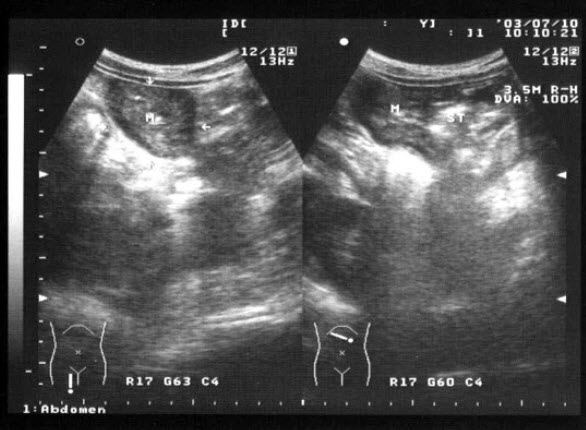

3、单项选择题

男,18岁,外伤1小时就诊。结合超声声像图,诊断为()

A.脾外伤血肿

B.脾淋巴管瘤

C.膈下积液

D.脾皮样囊肿

E.脾血管瘤